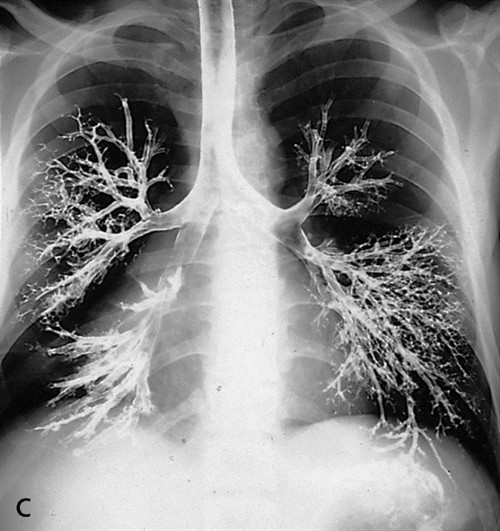

In anatomy lab we started dissection of the thorax. It was fascinating! We saw the mediastinum, the heart and the lungs. We followed this up in the lecture by discussing the anatomy of the lungs and looking at a bronchogram. I wanted to include this picture because it amazed me. The bronchi reminded me of the roots of a tree. And just like the roots of the tree, the bronchi are essential to our vitality as they allow us to intake oxygen during breathing.

A bronchogram is an X-ray taken after the patient receives an intravenous injection of a radiopaque substance. That substance allows us to see the area injected because the X-rays cannot pass through it. Bones are projected on an X-ray because X-rays cannot pass through them. We also mentioned the patient position for a chest X-ray.

It was a brief review of information we learned last trimester in radiology. The patient has to stand facing the film or cassette for a chest X-ray. We want the patient positioned so what we want to see is closest to the film or cassette.